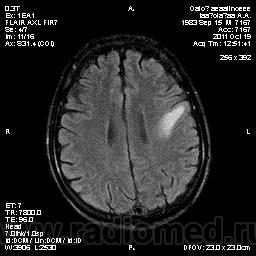

Колеги, спасибо за высказывания. В данном случае про наркоманский анамнез указано не спроста... Есть мнение, что в этом лежит точка отсчета.... По поводу абсцесса и гематомы - не согласен; по поводу первого - нет соответствющей клиники, по поводу второго - не характерна локализация и сигнальные характеристики. Не буду томить общественность касательно собственного мнения. Есть две гипотезы, о которых думается в данном случае: прогрессирующая лейкоэнцефалопатия и новообразование... Но без контраста их не разрешить...

Наркоманский анамнез -скорее первое?

пожалуй "первое", но в отношении "второго"смущает "круглит" на вершине "воспалительной демиелинизации", который она (демиелинизация) так странно обходит...

Имеются  в виду последние 2 картинки?Мне тоже так показалось.А почему контрастирования не будет?Чем контрастируете?